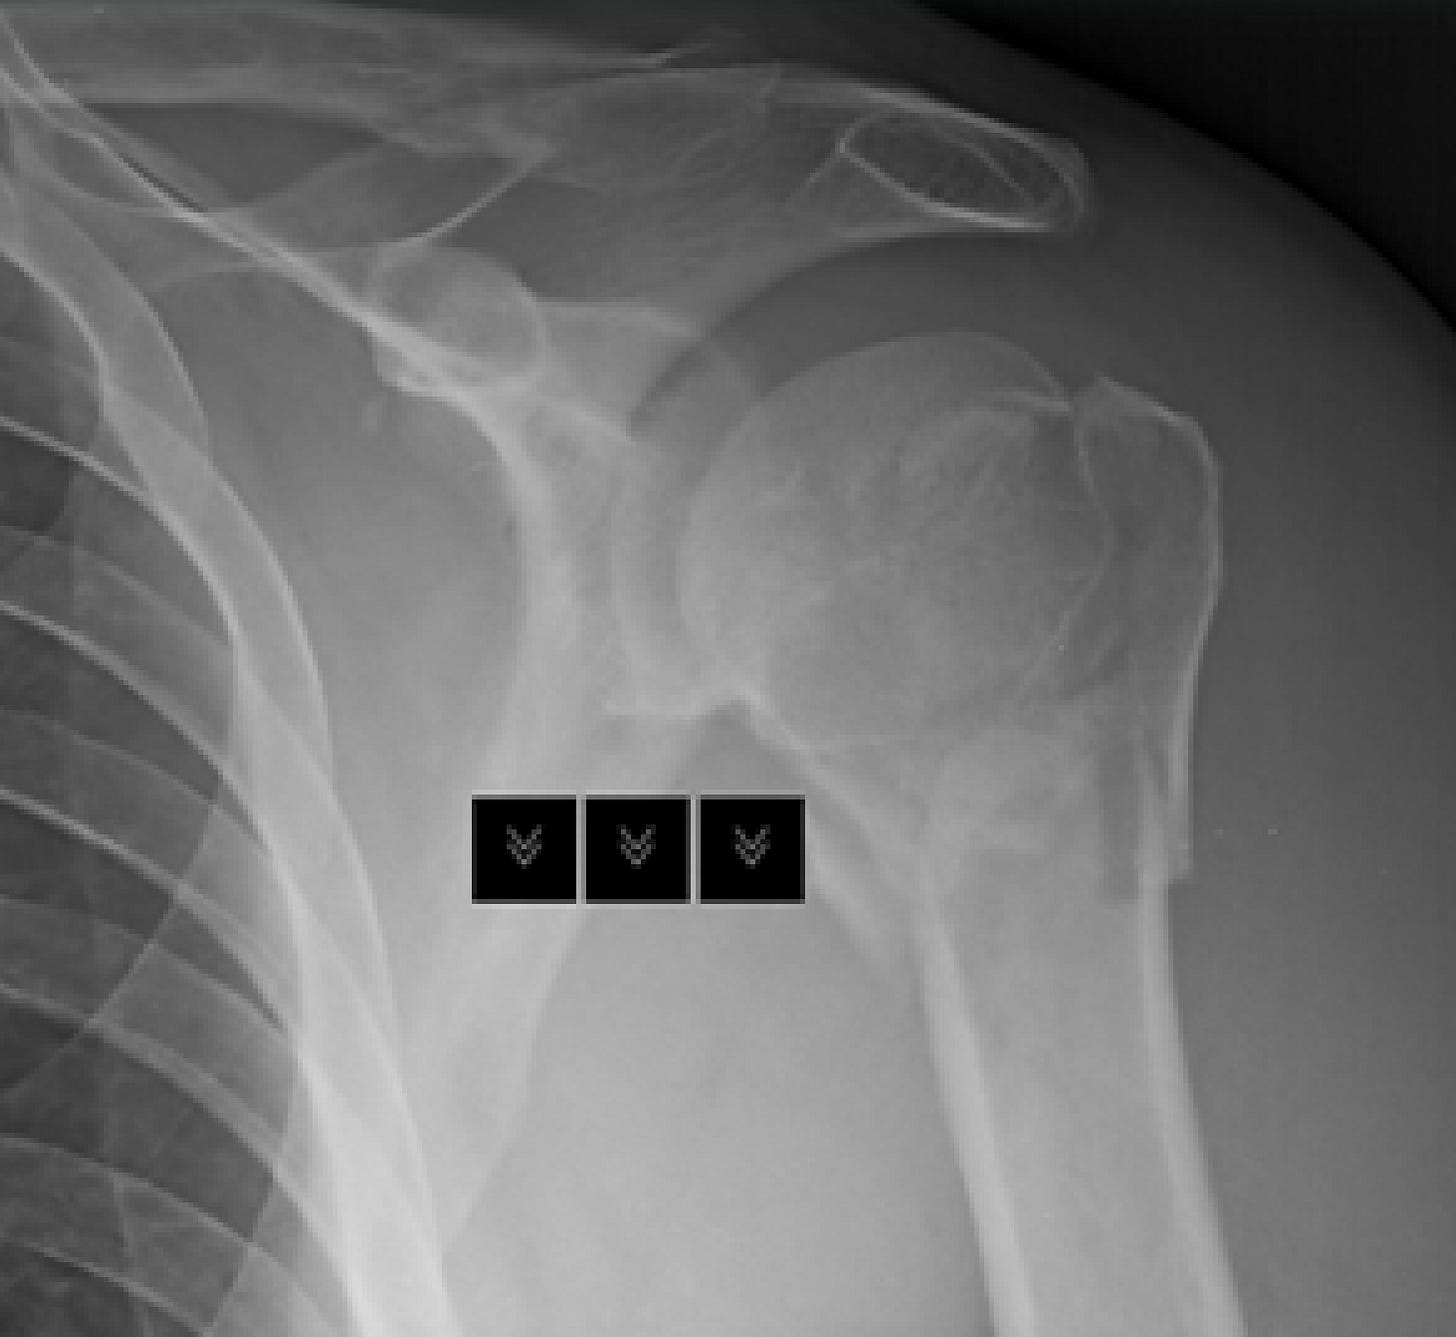

I love life and in between lazy stints on my bean bags watching trash I try to get the most out of it. I shattered my humeral head (shoulder) a bit under four weeks ago. Diving in my pool as I’d done for eight years. Entered water wrong, wrist that normally absorbs downward energy slips, elbow hit bottom, shoulder shattered.

I have been laid up for four weeks. Worst pain of my life and I’ve done some very painful things. I’m just now able to type without causing pain. All of my plans for the last four weeks gone. Most of my plans for the next three to six months gone. I’m told by humans and AI it’s a SIX TO TWELVE (6-12) MONTH recovery.